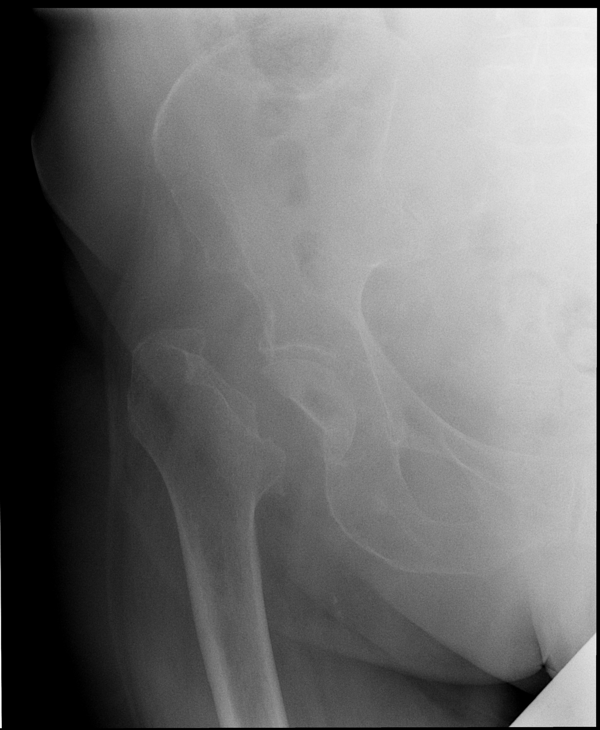

Перелом шейки бедренной кости.

Наиболее частым переломом, встречающимся у людей старше 65 лет, является перелом шейки бедренной кости, или попросту шейки бедра. Женщины страдают этой патологией несколько чаще мужчин. Перелом шейки бедра – инвалидизирующая травма, требующая своевременной диагностики и квалифицированной травматологической помощи. К переломам шейки бедра по сходству течения, заживления и прогнозам относят:

Решающее значение в установлении диагноза перелома шейки бедра имеет рентгенография тазобедренного сустава. У пожилых пациентов приведенные выше симптомы могут проявляться нечетко, а такие заболевания как инсульт или невропатия, вообще, не позволят поставить правильный диагноз без рентгена. Где сделать рентген? Перелом шейки бедра всегда сопровождается сильной болью, поэтому любые лишние движения оборачиваются новыми мучениями, а сопутствующие заболевания внутренних органов усугубляют ситуацию! Решение есть - воспользоваться уникальной услугой – цифровой рентген на дому. К вам приедет врач рентгенолог-травматолог, который выполнит весь комплекс лечебно-диагностических мероприятий и подробно расскажет, что делать дальше.